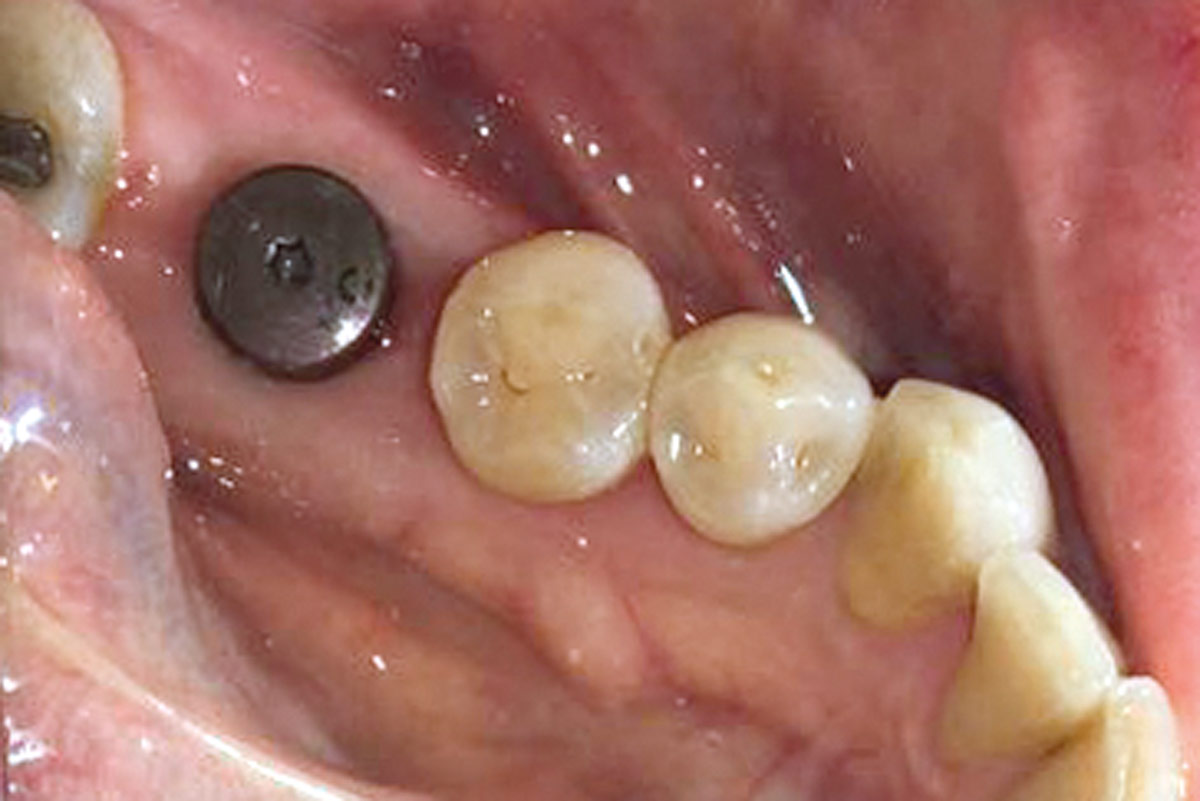

13/19 - Healing 3 month post-op

Immediate implant placement using maxresorb® - Dr. Alejandro Signorio